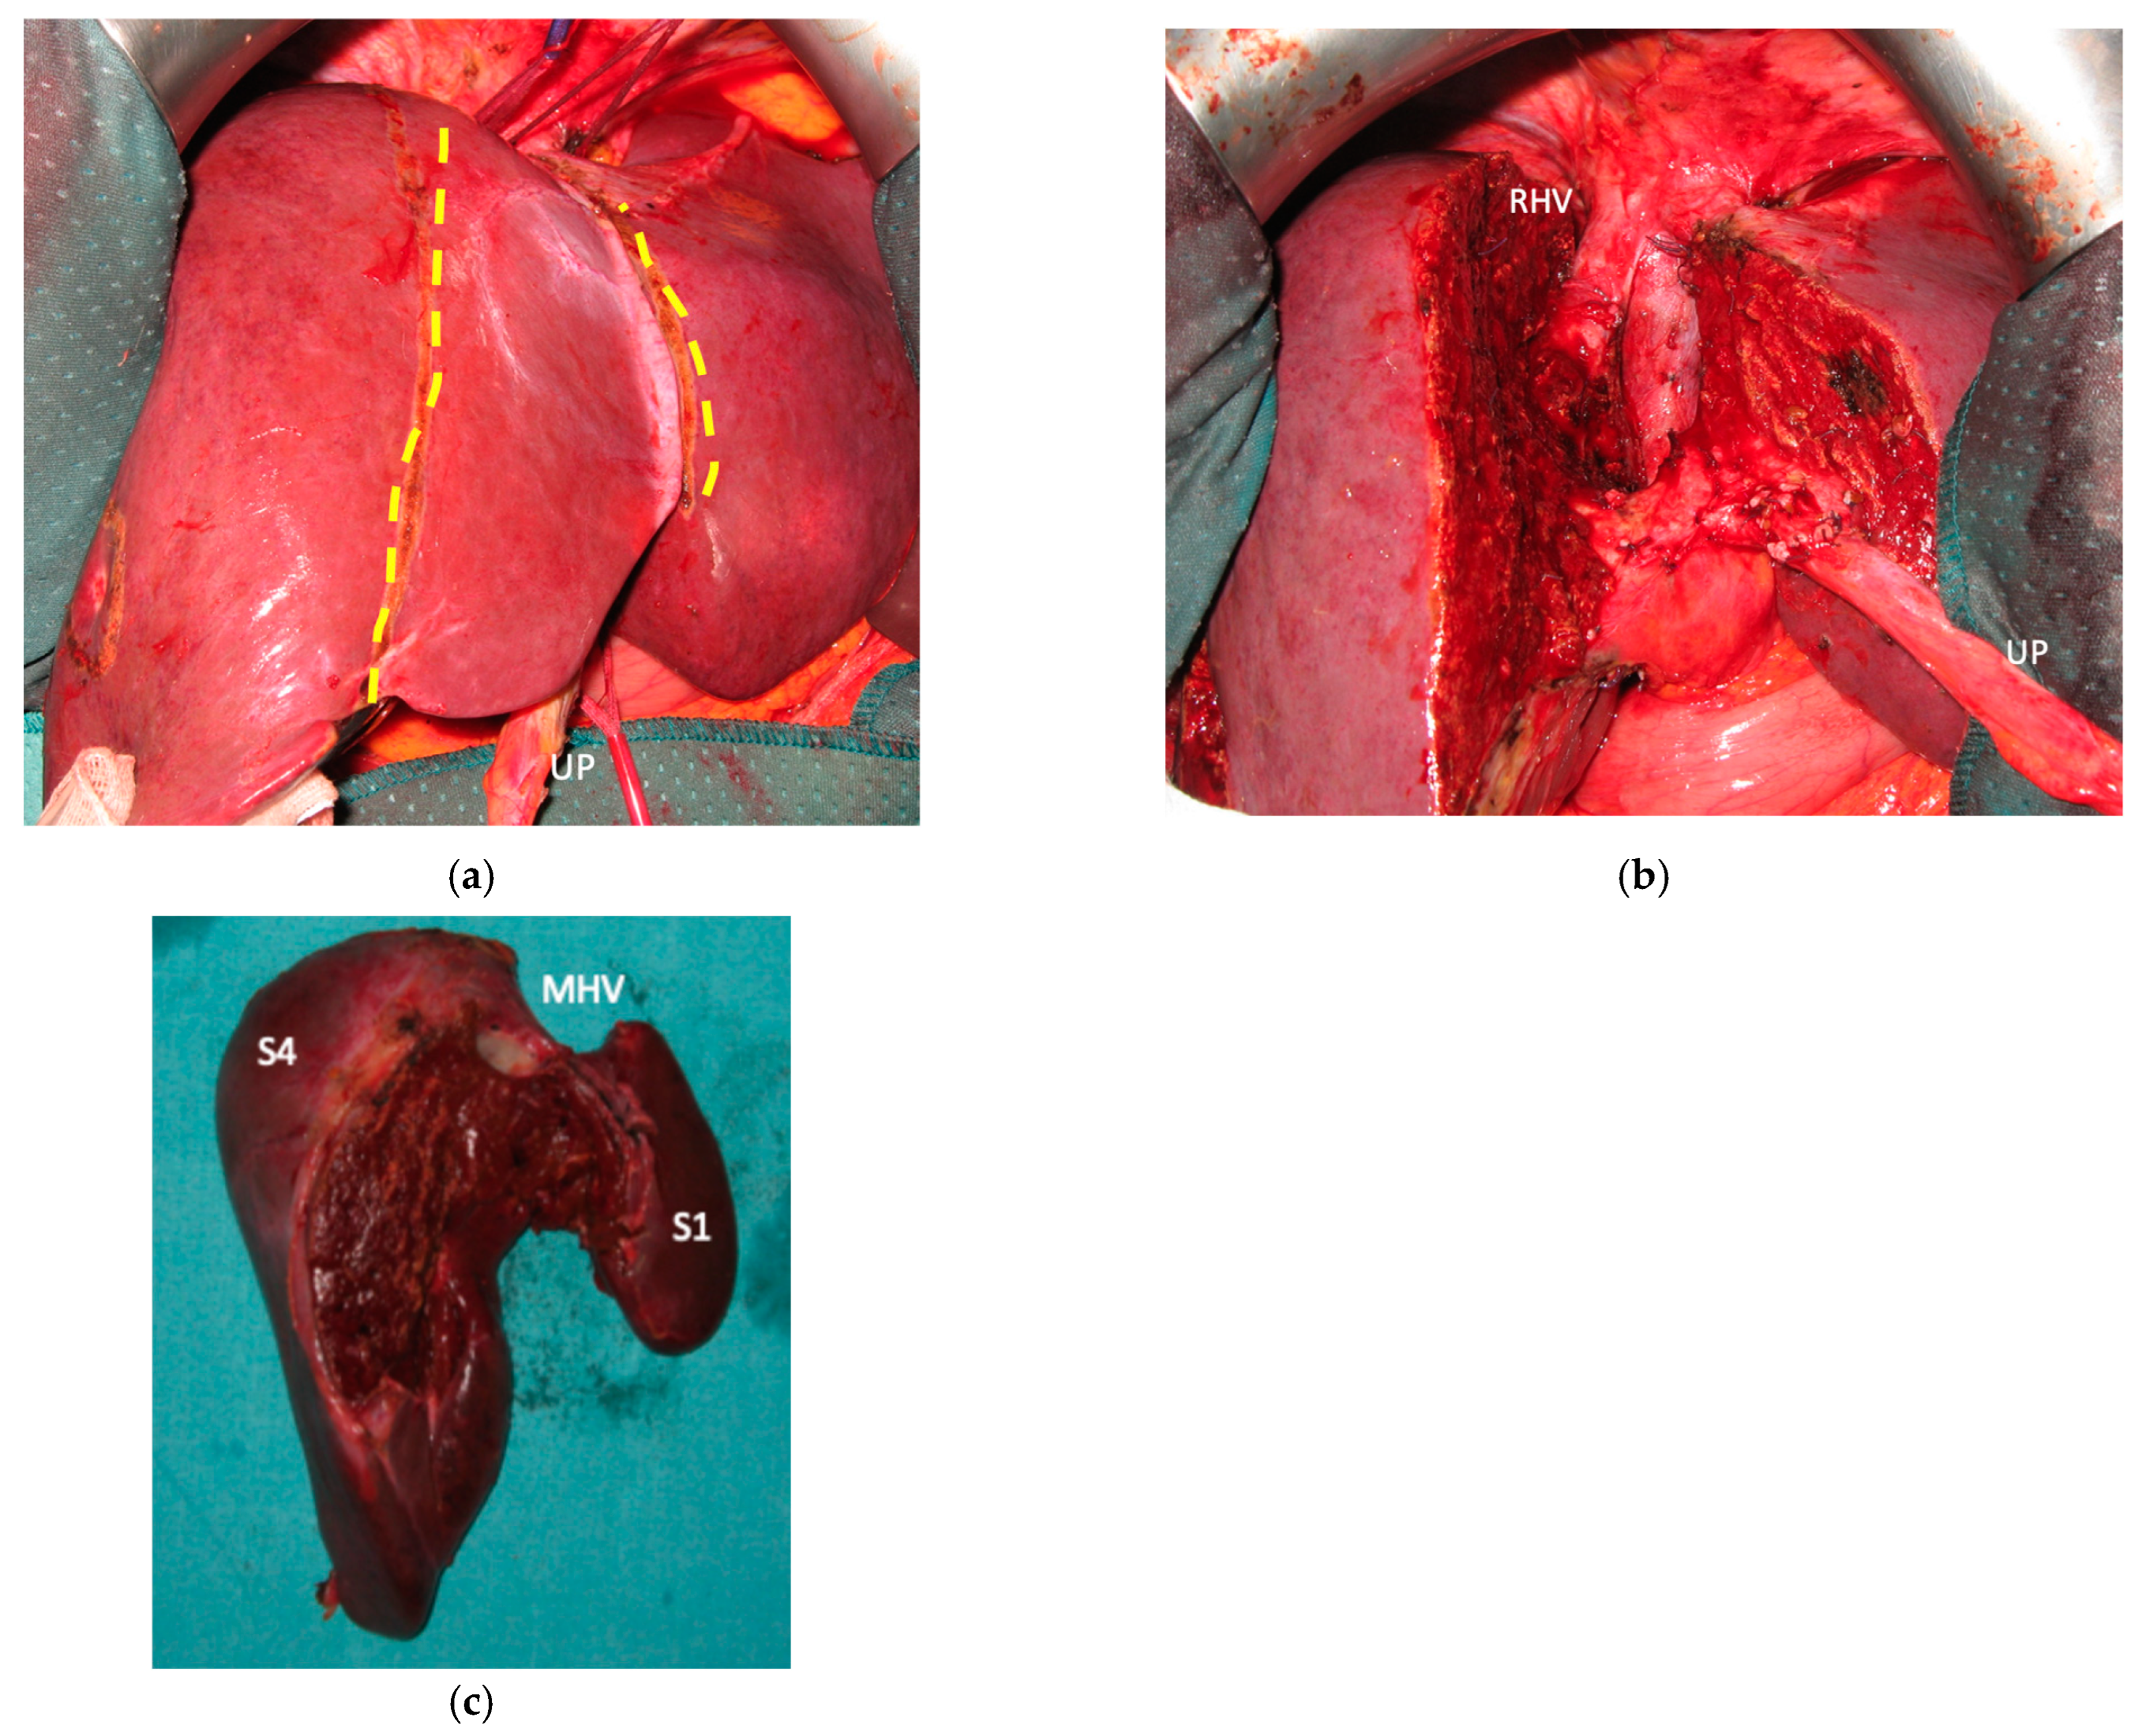

Liver partition was obtained with a major mesohepatectomy in two cases with anatomical resection of S1/S4/S8 (en-bloc with biliary tree in one, see Figure 5).

Figure 4. Intraoperative field images of a vessel-guided mesohepatectomy of S1/S4 en-bloc with MHV for liver partition (MLP). MLP is a minor resection (less than 3 adjacent liver segments) inducing a major hepatic scaffold modification transforming the liver into a paired organ. (a) Liver transection lines (yellow dotted lines). (b) Intraoperative view of the two livers. (c) Surgical specimen of S4/S1 en-bloc with MHV corresponding to a volume of 205 mL. Abbreviations: MLP: mesohepatectomy for liver partition; MHV: middle hepatic vein; RHV: right hepatic vein; S: segment; GP: glissonean pedicle; UP: umbilical portion.